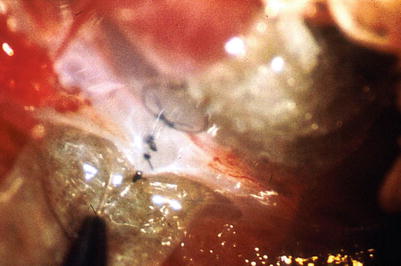

Lympho-lymphatic anastomoses have been investigated also by electron microscopy. Electron microscopy investigations revealed a smooth inner surface at the site of the anastomosis. In Fig. 2.11, the area of a lympho-lymphatic anastomosis is opened by an oblique cut of the vessel. The nonabsorbable suture material marks the site of the anastomosis. The vessel is stabilized by a small round insert for the electron microscopy preparation. The anastomosis is patent, the inner surface is smooth, and the endothelial layer is continued from one vessel to the other (Fig. 2.11).

Fig 2.11

Scanning electron microscopy (oblique cut of the anastomosing site) 11 weeks after lympho-lymphatic anastomoses (nonabsorbable suture material), patent anastomosis, smooth inner surface continuous endothelial layer